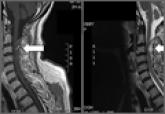

ArticleSpontaneous Cervical Spinal Epidural Hematoma Author:Katie Rinne, MBBSPublish date: May 4, 2016 Read More